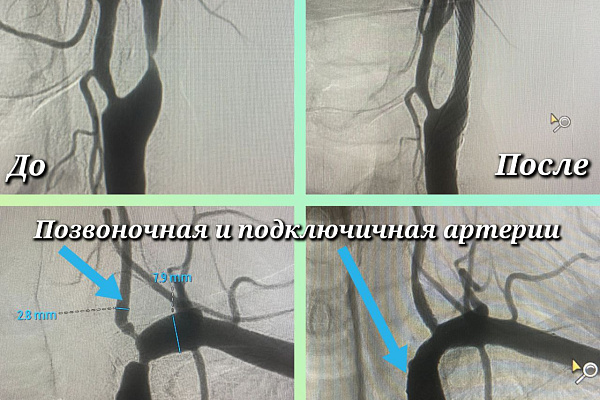

Чтобы в первую очередь избежать инсульта, оперативное лечение Максим Бессмертных начал с сонной артерии. Сначала восстановил её проходимость специальным баллонным катетером, а затем для предотвращения повторной окклюзии установил стент. Те же самые манипуляции выполнены на подключичной и позвоночной артерии. Всё это – за одну операцию. Малоинвазивное рентгенэндоваскулярное вмешательство длилось около двух часов.